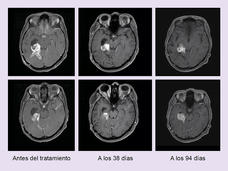

La terapia dirigida es mejor que la quimioterapia para algunos niños con cáncer de encéfalo

Los resultados del estudio mostraron que la combinación de dabrafenib (Taflinar) y trametinib (Mekinist) achicó más tumores de encéfalo, controló por más tiempo los tumores y causó menos efectos secundarios que la quimioterapia. Todos los niños tenían un glioma con una mutación BRAF V600 que no se podía extirpar o que había vuelto después de la cirugía.